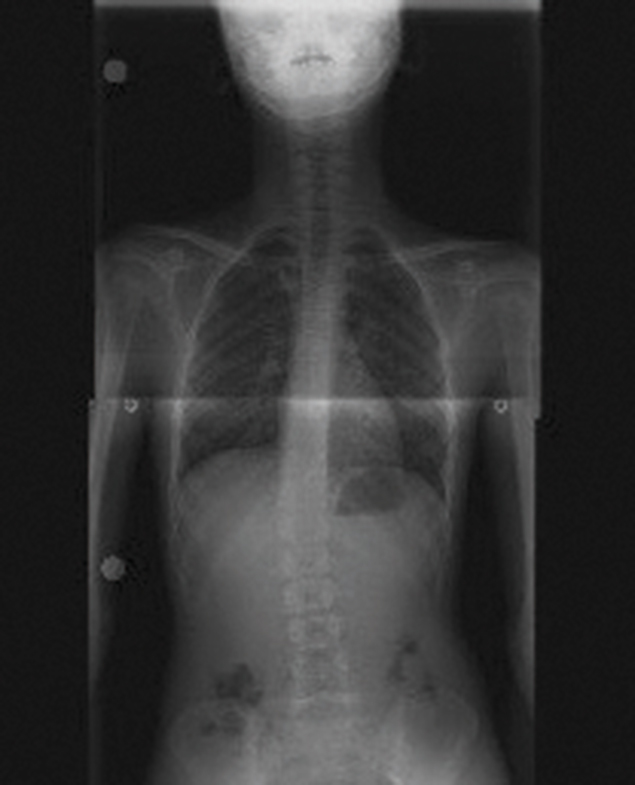

Ünü Kocaeli sınırlarını aşan fizyoterapist Elif Akıncı’nın geliştirdiği Rubatonik Pilates yöntemi mucizeler yaratıyor. Omurga rahatsızlıklarından kaynaklanan sorunların çözümünde oldukça etkili sonuçlar elde eden Elif Akıncı Pozitif Yaşam Merkezi’nin sahibi fizyoterapist Elif Akıncı, 1 yıl önce 18 derecelik skolyoz tanısıyla merkeze başvuran 15 yalındaki Ada Özkan’ın mucizeyi yaşamasını sağladı.

6 yaşından beri Kocaeli Gelişim Spor Kulübü’nde basketbol oynayan lise öğrencisi Ada Özkan, 1 yıl önce şiddetli ağrılar yaşamaya başladı. Ağrıları nedeniyle basketbol oynayamaz hale gelen Özkan, doktora gittiğinde 18 derecelik skolyozu olduğunu öğrendi. Ağrıları nedeniyle oturmakta, yürümekte ve uyumakta zorluk çeken Ada Özkan, sıkıntılarından kurtulmak için bir arayış içerisindeyken teyzesinin tavsiyesi üzerine fizyoterapist Elif Akıncı ile tanıştı. Elif Akıncı Pozitif Yaşam Merkezi’ne devam ettiği bir yılın sonunda hem hayatını zindan eden ağrılardan kurtulan hem de ara vermek zorunda kaldığı basketbola yeniden başlayan Özkan, yaşadığı değişimi şöyle anlattı:

Egzersizlere ilk başladığımda, merkeze haftanın 3 günü geliyordum. Elif Hanım, daha iyi sonuç almamız için böyle bir program oluşturmuştu. Daha sonra haftada iki kez birer saat egzersiz yapmaya başladık ve bir yılın sonundan adeta bir mucize oldu. Artık ağrılarımdan neredeyse tamamen kurtulmuştum. Kontrol için doktora gittiğimde, skolyozumun ölçülemeyecek kadar gerilediğini söyledi.